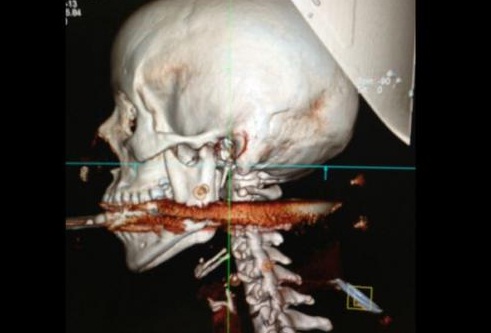

«Se puede decir que ella resucitó. Tuvo mucha suerte porque hay arterias que están en esa zona. Requirió mucho cuidado el retiro del arpón», que le atravesó la boca y se le alojó en la primera vértebra cervical, dijo a la televisora Globo News el cirujano plástico que la operó durante dos horas, Marcelo Amaral.

«El arpón le atravesó la faringe, le rompió dos molares y se alojó en la primera vértebra cervical. Unos milímetros más y habría quedado tetrapléjica o estaría muerta», señaló el cirujano, quien necesitó la ayuda de un equipo médico para retirar el arpón.